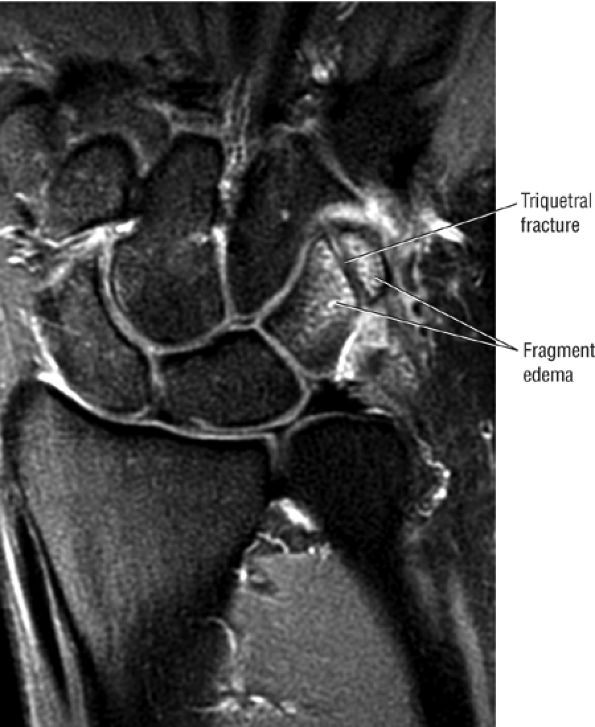

|